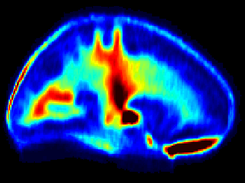

Normative myelin water atlas was created by co-registering and averaging myelin images in MNI space from 50 healthy brains to depict the population mean and variability of the myelin content in the brain. The myelin images of individual subjects were acquired using myelin water imaging. Details about myelin water imaging technique and its analysis can be found here: https://mriresearch.med.ubc.ca/news-projects/myelin-water-fraction/. The created myelin water atlas with its standard deviation can be used as a reference for your own studies related to myelin. A full description of this work can be found in this paper: https://www.ncbi.nlm.nih.gov/pubmed/31347238.

• Myelin water imaging

• Atlas for normal myelin content